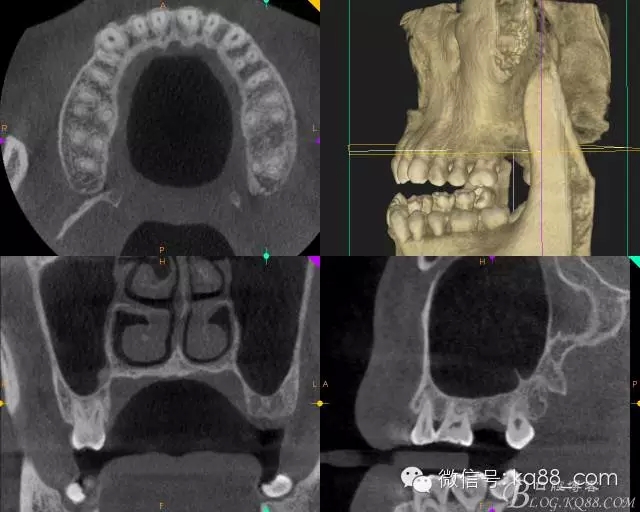

術前拍攝CT發(fā)現(xiàn)該處牙槽骨高度不足需要進行內(nèi)提升手術,但是 CT上看骨的寬度很好,所以決定采用微創(chuàng)植入。

術前的CT影像